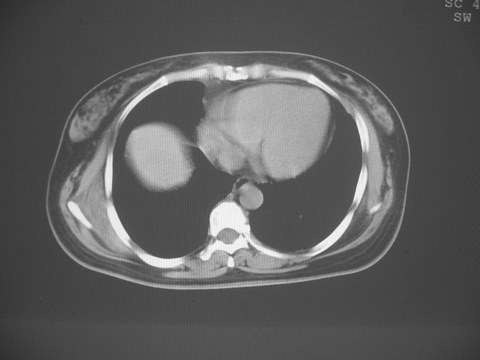

无意中发现右背部肩胛下缘半球状突起,无红,热,痛感觉。拍平片未见异常。ct发现右肩胛下角深层新月型软组织肿胀,ct值-50至15,大家看看是什么性质,来源,初步考虑来源于下后锯肿,考虑下后锯肌肿胀,可是病人无明确外伤史,也不疼痛

三、弹性纤维瘤影像

典型位于背部,在肩胛下角和胸壁软组织之间,肿瘤表面为菱形肌和背阔肌所被覆深部,紧邻肋骨和肋间肌,呈半圆形或扁豆状,宽基底与胸壁相交,边界比较清楚,相邻的肌肉和肋骨无侵蚀,部分病变与其表面的临近肌肉之间可受压呈弧形的脂肪界面,肿瘤周围软组织无水肿。

从mr表现可以推断ct影像,即肿块呈软组织密度,病灶内可出现脂肪密度的低密度影。

大家注意下 这个病人有乳腺增生,和肩胛下病变没什么关系,但ct下发现乳腺增生的好象不多,因为她有乳腺增生病史,所以才有所注意